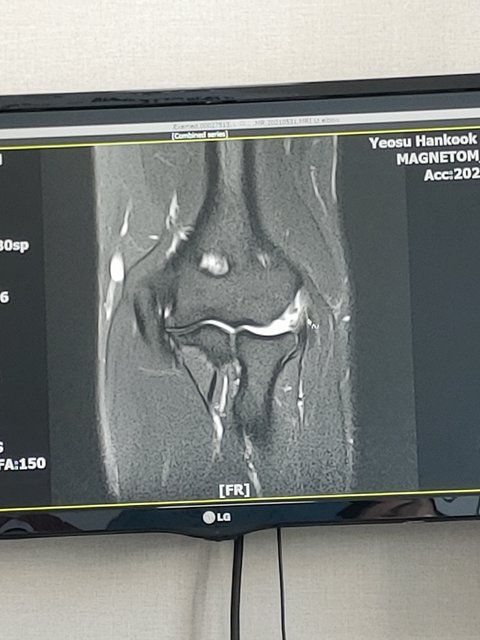

제가 사는 지역은 큰 병원이 없어 이송된 병원에서 치료가 불가하다 판단되어 다른 지역의 대학병원으로 이송되어왔고, 의사선생님은 저에게, 왼쪽 갈비뼈가 모두 부러짐과 동시에 비장이 파열 되었고, 오른쪽 무릎 파열, 왼쪽 팔 인대 끊어짐, 또 척추가 일부 손상되었지만 사고나실 때 몸을 웅크리고 계셨는지 신경은 살아있어서 다행히 걸을 수 있다고 무시무시한 말씀들을 덤덤하고 희망차게 전해주셨습니다. 오랜 재활이 필요하겠지만 오토바이 그것도 음주운전자가 낸 사고에 이정도면 죽지 않는걸 다행으로 생각하셔야 한다는 말씀과 함께요.

온 몸이 찢어질 듯이 아픈 통증보다, CT며 MRI며 하루걸러 하는 검사들이나 몇 번씩 이어지는 수술들보다, 다시 제대로 걷기 위해 재활했던 그 시간들보다도 저를 힘들게 했던 건 배변활동을 제 자력으로 할 수 없다는 것이었습니다. 세세히 다 서술할 순 없겠지만 정말이지 수치스럽고 너무너무 끔찍했습니다. 기저귀를 차고 있어야 했던 기간동안 아내와 어머니, 누나가 번갈아가며 제 병수발을 들었는데 이게 도대체 뭐하는 짓인가 싶었습니다. 나중에는 그 시간이 두려워 밥도 최소한으로만 먹었습니다. 왜 이렇게 못먹냐 먹고 싶은거 없냐는 아내의 말에 제대로 말도 못하고 신경질도 엄청 냈습니다. 괜찮을거다 금방 나을거다라는 위로의 말을 들으면 본인일 아니니 쉽게 말하는거 같고 듣기 싫었습니다. 점점더 정신적으로도 피폐해져갔고 저의 피폐함은 저만큼이나 가장 힘들 제 아내도 말라가게 했습니다. 지금 얘기하면 본인이 백번 잘못하신일이라 말씀하십니다만, 당시 어머니께서 아내에게도 모진말씀 많이 하셨고 그렇게 저로인해 이 사고로 인해 힘들어하는 아내를 보며 아내에게 진지하게 내가 너를 놔줘야 할 거 같다며 이혼에 대한 얘기를 꺼낸적도 있습니다.

전치 12주 진단, 무릎은 평생 장해, 팔과 갈비뼈 등은 후유장해 5년 진단을 받고 8개월의 병원생활 끝에 통원이 가능해졌어도, 먹고 사는 문제가 기다리고 있었습니다. 제가 병원에 있는 동안 거래처들은 이미 다 떠나간 뒤였고, 코로나의 타격에도 어떻게든 악착같이 버텨보던 아내의 카페는 제 병간호로 인해 폐업을 하게 되었습니다.